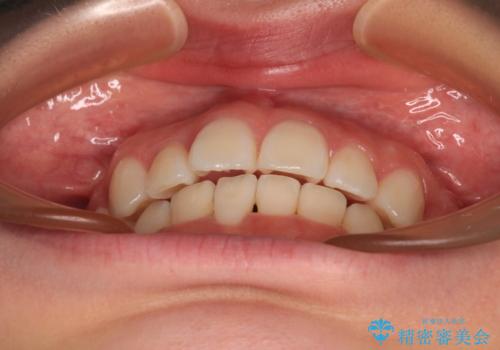

- 歯のデコボコや八重歯、クロスバイトを気にして来院された患者様です。

上下の骨格での左右差が小さかったことと、抜歯矯正であったことで、上下正中の位置をきれいに合わせることができました。